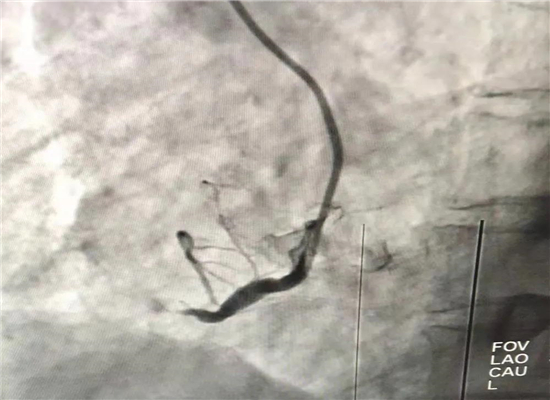

介入手术前

介入手术后